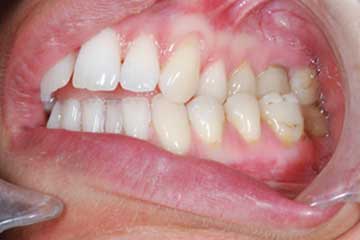

Trattamento ortodontico nell'adulto con intrusione del I° molare superiore mediante l'utilizzo di mini impianti

Trattamento ortodontico nell'adulto